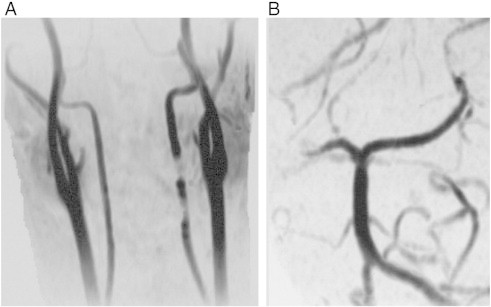

Fig 5.

MRA demonstrates recanalized left VA and occluded right P2.